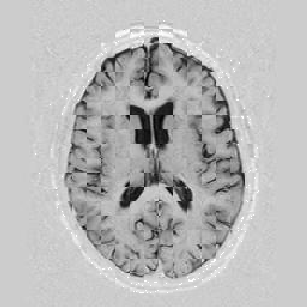

Another larger group of experiments enabled me to study the effects of multi-scale NRR. The results are shown in the form of chequerboard images in Figure [*]. In terms of resolution levels, higher numbers mean that the images are coarser.

Figure: Multi-scale NRR (increasing resolution). From left to right, top then bottom:before NRR; after 5 iterations of NRR at level 2 (higher is coarser); after another 5 iterations of NRR at level 1.